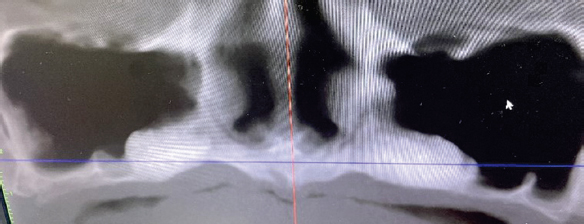

После анализа конкретной клинической ситуации, и оценки анатомических особенностей строения верхней челюсти (рис. 2) было принято решение об увеличении объема костной ткани в области гайморовых пазух и дна полости носа перед установкой имплантатов на верхней челюсти (рис. 3).

Рис. 2. Компьютерная томограмма верхней челюсти до начала стоматологического лечения

Fig. 2. Computed tomography of the upper jaw before dental treatment